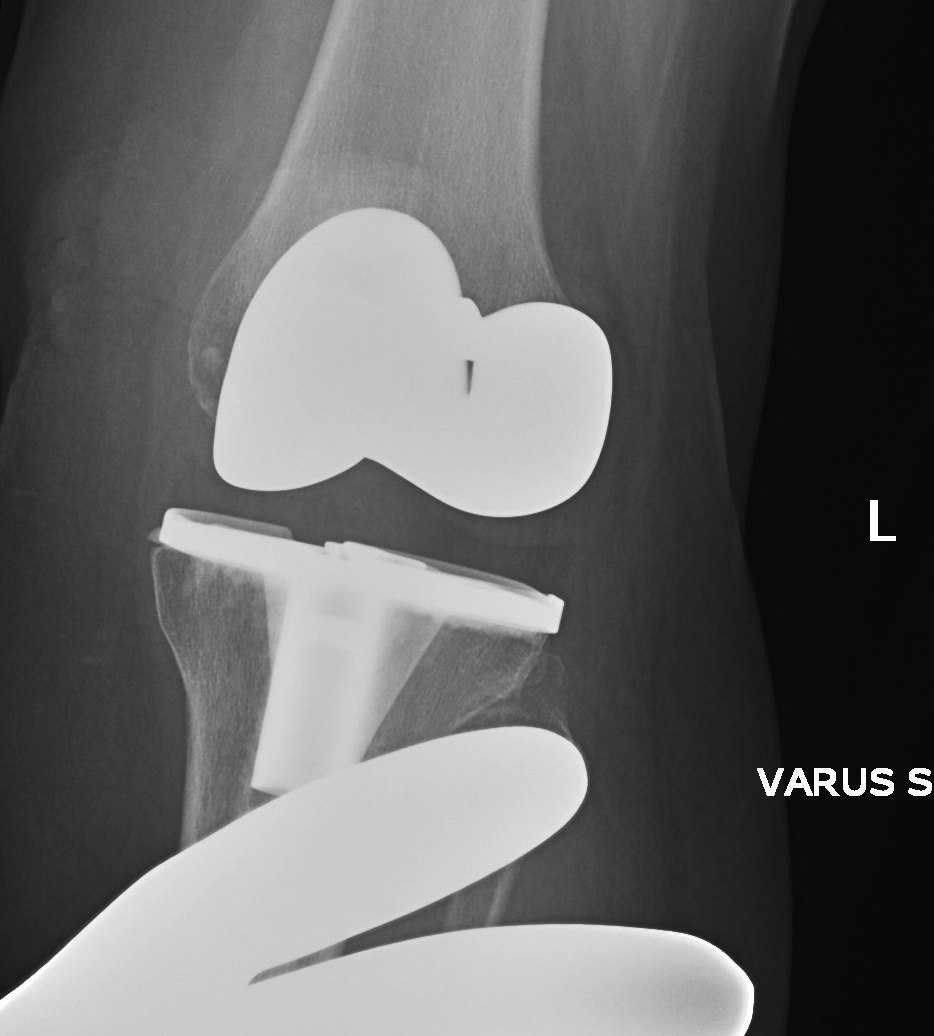

2. Varus Valgus Instability

Varus-Valgus instability

B. Failure to balance knee

Cause

- under release deformity in the concavity

Management

- increase poly thickness, further releases in concavity